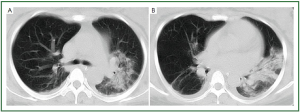

According to our inclusion criteria, all the patients had CT evidence of lung abnormalities consistent with influenza H1N1 pneumonia. The lung lesions were of typical virus infection, including ground-glass opacity (hazy areas of increased attenuation without obscuration of the underlying vessels), consolidation (homogeneous opacification of the parenchyma with obscuration of the underlying vessels), reticular opacities, linear opacities, interlobular septal thickening, and mixed pattern (Figures 1,2).

Figure 1. 28-year-old woman with H1N1 viral pneumonia. No history of chronic pulmonary disease. Chest CT was obtained day 6 after onset of influenza symptoms. CT images (A-B) demonstrate ground-glass opacities and consolidation predominantly in the middle zone and lower zone of the left lung, and minor patchy ground-glass opacities in the lower zone of the right lung. There is bilateral mild pleural involvement. The lung lesion score is 8.

Figure 2. 44-year-old man with H1N1 viral pneumonia in critical condition. No history of chronic pulmonary disease. Chest CT was obtained 6 days after the onset of the influenza symptoms. Bilateral and widespread ground-glass opacities in all six lung zones are demonstrated (A-D). There is bilateral mild pleural effusion. The chest lesion score is 19.